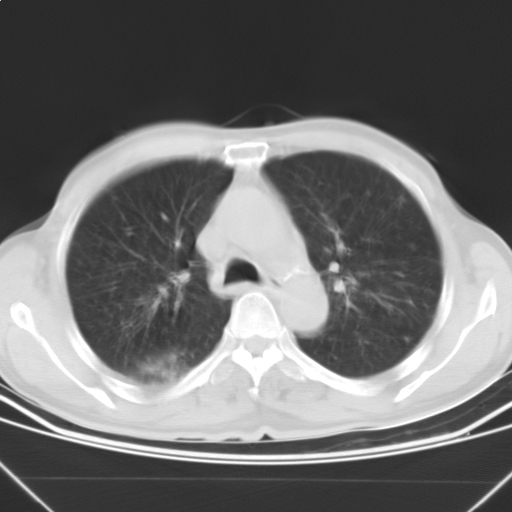

以下是引用随光逐影在2009-5-1 13:53:00的发言:[br]考虑为:1)两肺血行播散型肺结核;2)右肺下叶炎症感染。3)右侧胸膜增厚。